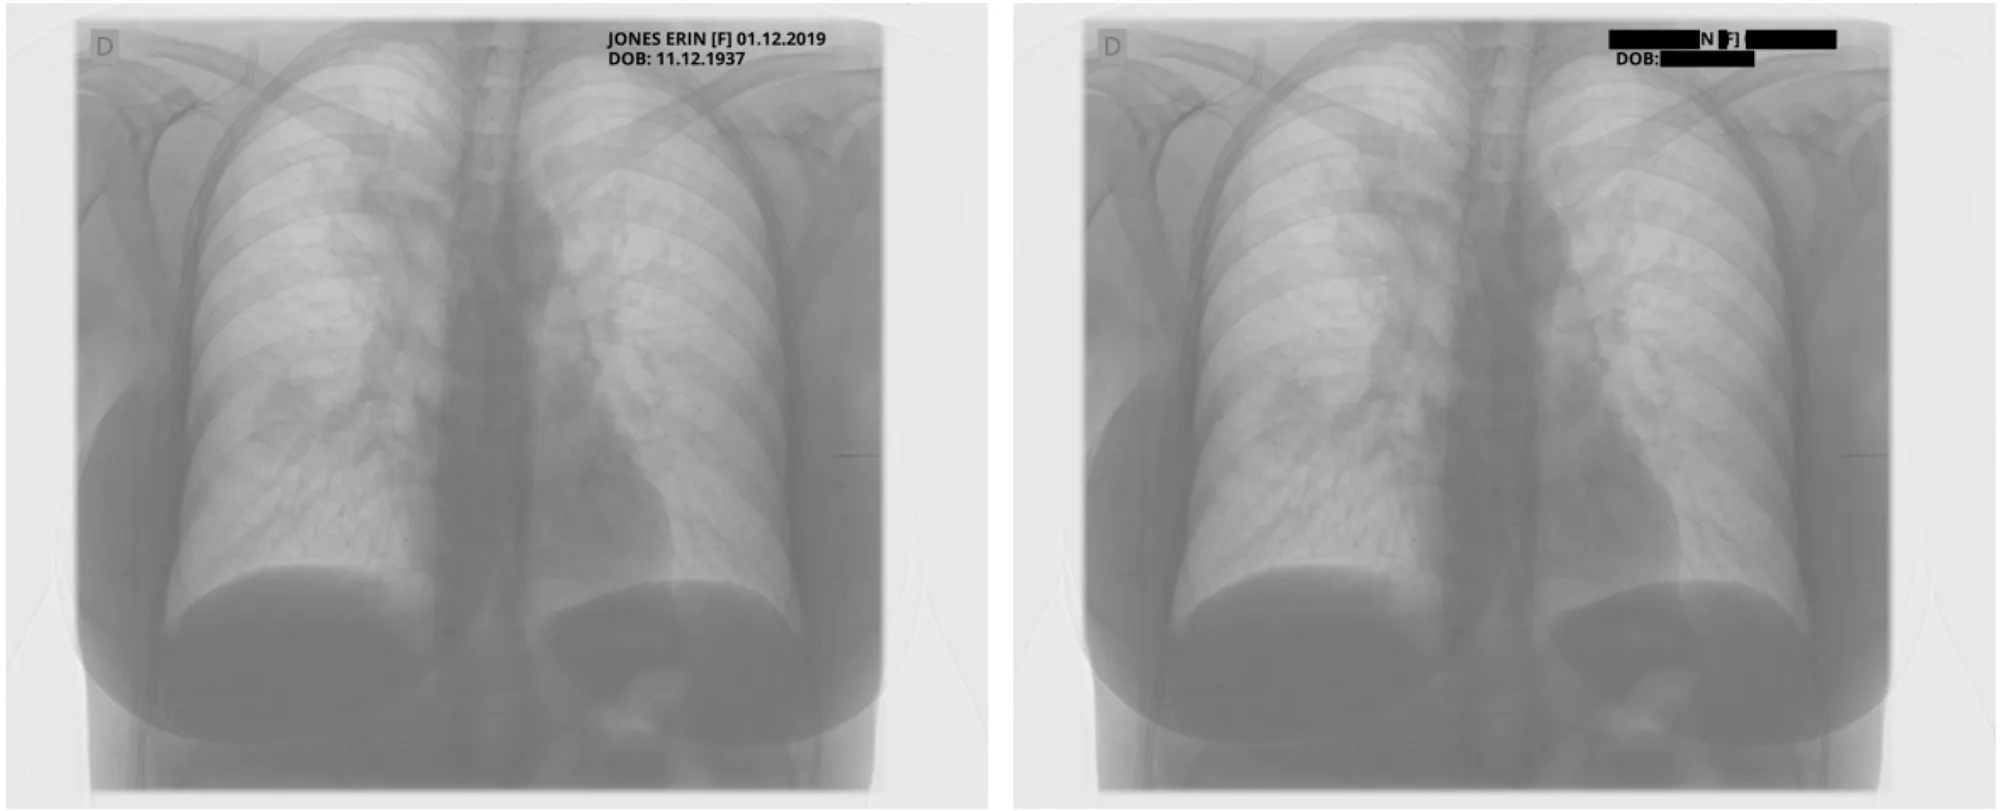

Metadata DeIdentification Original ( Left ) -> DeIdentified ( Right )

Sample Pixel Result 1

Sample Pixel Result 2

Sample Pixel Result 3